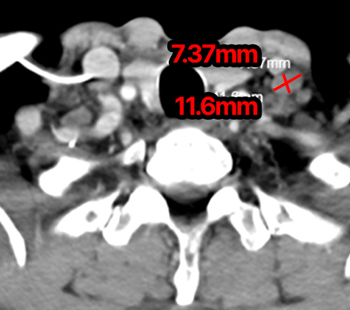

2024.1.30 치료 전

2024.5.21 치료 1개월 후

※ 동일한 조건에서 촬영된(사진에 대한 별도 조작이 처리되지 않은) 본원에서 진료 및 치료를 받으신 고객(들)의 사진입니다.

사진의 결과는 사례에 기반한 참고 자료로, 개인별 치료 결과는 상이할 수 있습니다.

또한 치료 후에는 홍반, 열감, 피로감, 근육통, 저혈습 등 부작용이 발생할 수 있습니다.